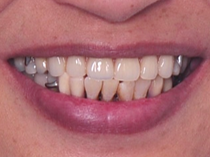

治療後

患者見證分享

陳阿姨裝上假牙後,除了吃東西變得比較方便之外,整個牙齒門面看起來也比較漂亮了!

之前都不太敢將嘴巴張太大,現在可以開心地大笑,非常開心~ 治療完成後三個月的後續追蹤,陳阿姨表示都很認真的在清潔牙齒,假牙也用得很習慣!